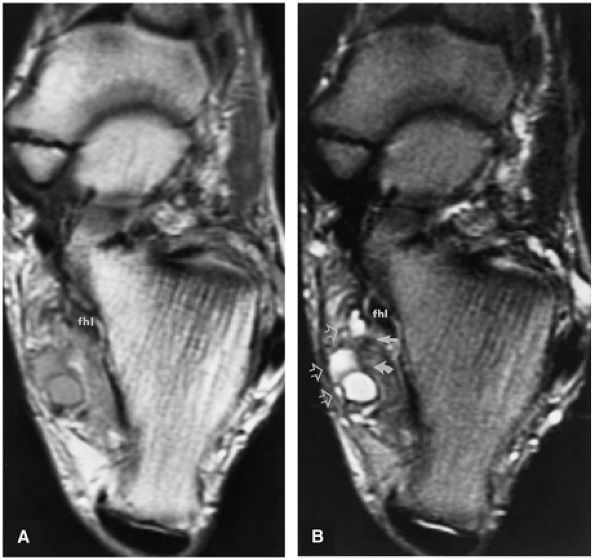

FIGURE 5.9 ● FLEXOR HALLUCIS LONGUS The flexor hallucis longus (FHL) flexes the great toe and plantarflexes the foot. The FHL is susceptible to injury during extremes of ankle plantarflexion and metatarsophalangeal dorsiflexion. The proximal sheath, 10 to 12 cm in length, has no mesotenon and may communicate with both the ankle joint and the sheaths of the flexor digitorum longus and tibialis posterior.

|